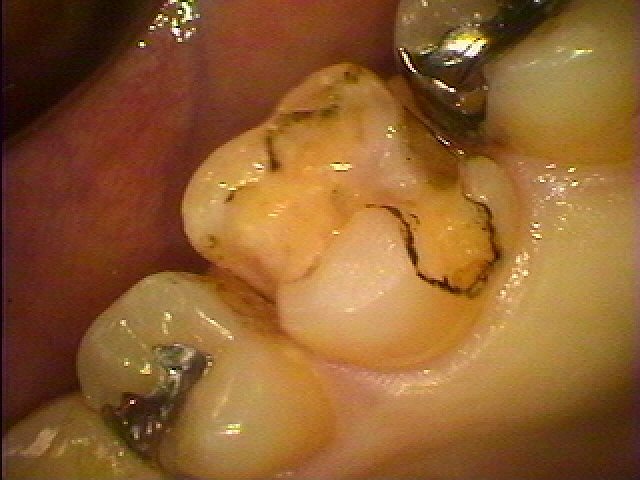

左上6番のインレーを外して虫歯治療を行っていきます セレックプライムスキャンを用いたセラミック治療|お知らせ |広島市安佐南区の歯科医院 左上6番のインレーを外して虫歯治療を行っていきます セレックプライムスキャンを用いたセラミック治療 トップ お知らせ・ブログ お知らせ 左上6番のインレーを外して虫歯治療を行っていきます セレックプライムスキャンを用いたセラミック治療 左上6番のインレーを外して虫歯治療を行っていきます セレックプライムスキャンを用いたセラミック治療 銀歯を外していきます この銀歯を白くしたいとのこと 銀歯を外していきました ひどくはないですが少し悪くなっています 虫歯を除去して型取りを行います セレックセラミックにて修復しています このようにきれいな白いセラミックが入りました 喜んでいただきました Web診療予約 初めての方へ 選ばれ続ける理由 院内設備について 歯が痛いしみる一般歯科 歯がぐらぐらする歯周病 健康な歯を保ちたい予防歯科 子供の虫歯予防をしたい小児歯科 銀歯をセラミックに審美歯科 白い歯を目指しませんか?ホワイトニング 矯正専門医がいるので安心矯正歯科 抜けた歯を補いたいインプラント・入れ歯 医院案内 スタッフ紹介 メリィハウス歯科クリニックオフィシャルホームページ ラベンダー歯科クリニックオフィシャルホームページ お知らせ・ブログ ホーム 診療科目 一般歯科 歯周病治療 予防治療 小児歯科 審美治療 ホワイトニング 矯正歯科 入れ歯・インプラント マウスピース矯正 初めての方へ 院長・スタッフ 設備紹介 医院案内・アクセス メニューを閉じる